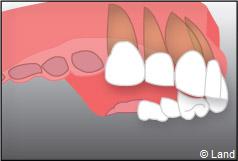

Exemple d’un implant unitaire pour remplacer une dent antérieure manquante.

Situation clinique initiale